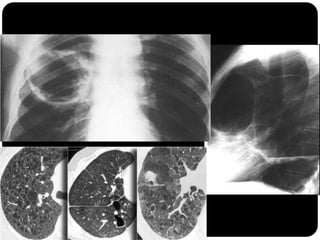

Bronquiectasias / bronquioloectasias

 Sinal do anel do sinete: artéria pulmonar

adjacente ao brônquio dilatado;

 Sinal do trilho do trem;